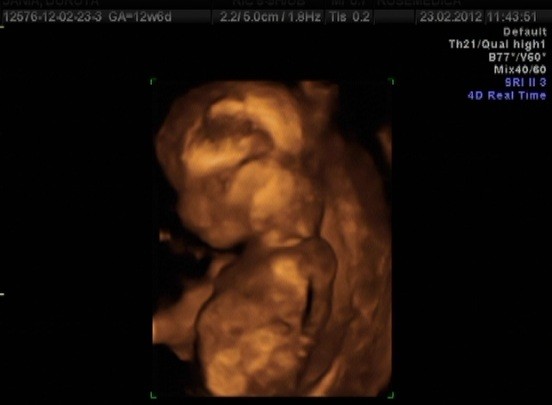

Dziękuję Wam KochaneMoże kiedyś zbiorę się i wytnę kawałek z filmu jak się Dzidzia drapie pogłowie... A to zdjątka (starałam się wybrać jak najlepsze kadry z filmu):

Zobacz załącznik 440449Zobacz załącznik 440450Zobacz załącznik 440451Zobacz załącznik 440452

ale przystojniaczki!!! :-)Zobacz załącznik 440453

a to moje z wczoraj) 13t = 6,34